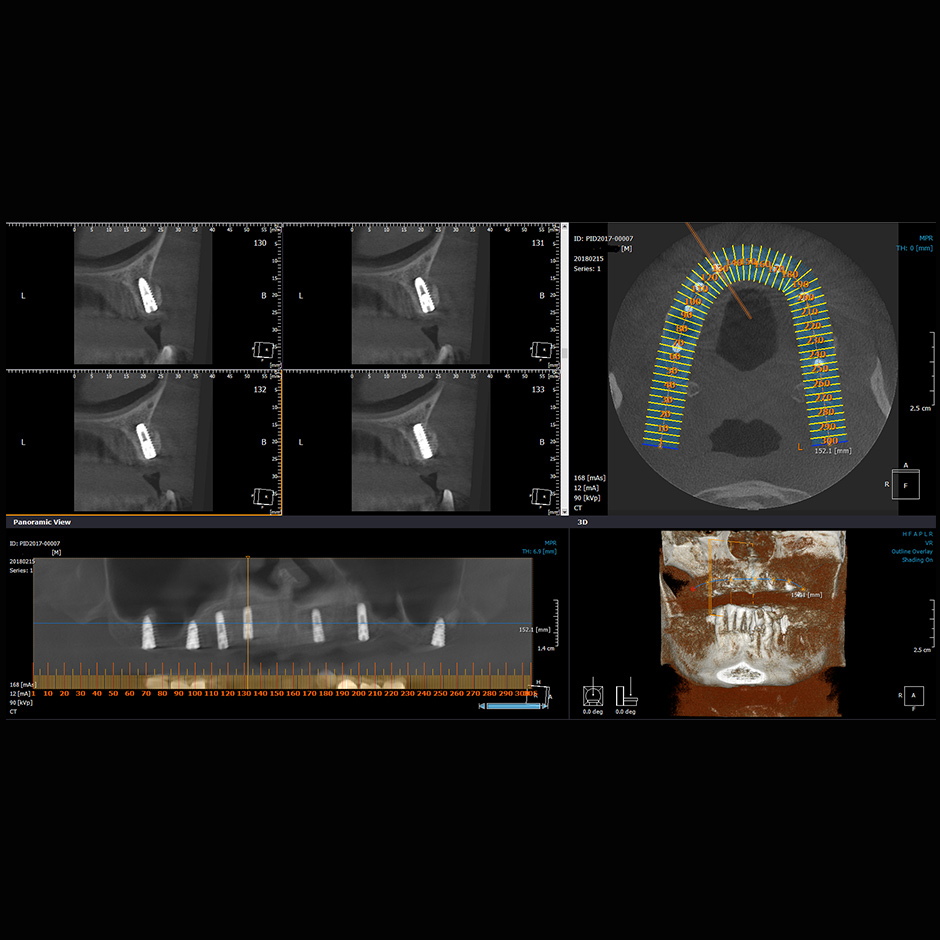

Implantáció röntgenkép

Különböző foghiányok esetén a legtöbb esetben az implantátumok beültetése adja a legmegfelelőbb megoldást a hiányzó fogak pótlásához. A szövetbarát, biokompatibilis titán implantátumok megjelenésével teljesen új dimenziók nyíltak a fogászatban.

Az implantátumokkal történő fogpótlásoknak köszönhetően a konzervatív lehetőségekhez képest mindig legalább egy szinttel jobb megoldást, így jobb életminőséget tudunk nyújtani. A kivehető fogpótlás helyett, akár fix, beragasztott, becsavarozott fogmű is készülhet (megfelelő számú műgyökér esetén). A mobilis kivehető fogpótlás, néhány implantátum beültetése esetén stabilizálható. Ha pedig egy-két fog hiányzik, akkor a foghiány helyére történő implantációval elkerülhető a hiányt határoló egészséges fogak lecsiszolása egy esetleges hídpótláshoz. Kisebb csontkínálat esetén pedig speciális helyzetű műgyökér beültetésével vagy csontpótlással érjük el a kívánt stabilitást.